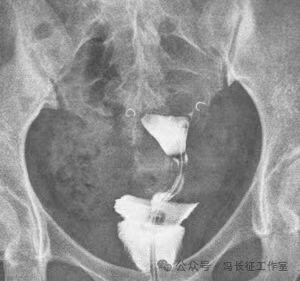

2014年5月在DSA上行输卵管近段介入栓塞术

栓塞前造影也显示双侧输卵管间质部和峡部细长,适合栓塞。于是向双侧输卵管间质部和峡部各栓塞一枚3/2(长2厘米,一端直径小2毫米另一端直径大是3毫米,就是向宝塔一样,有时被称为塔圈)弹簧圈。

微信图片_20240223171147(2).jpg